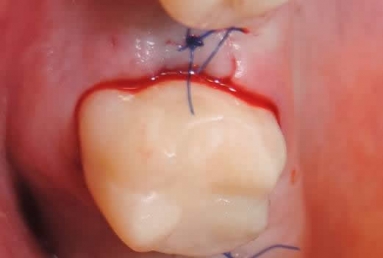

Dental implants upper second premolar, upper second molar